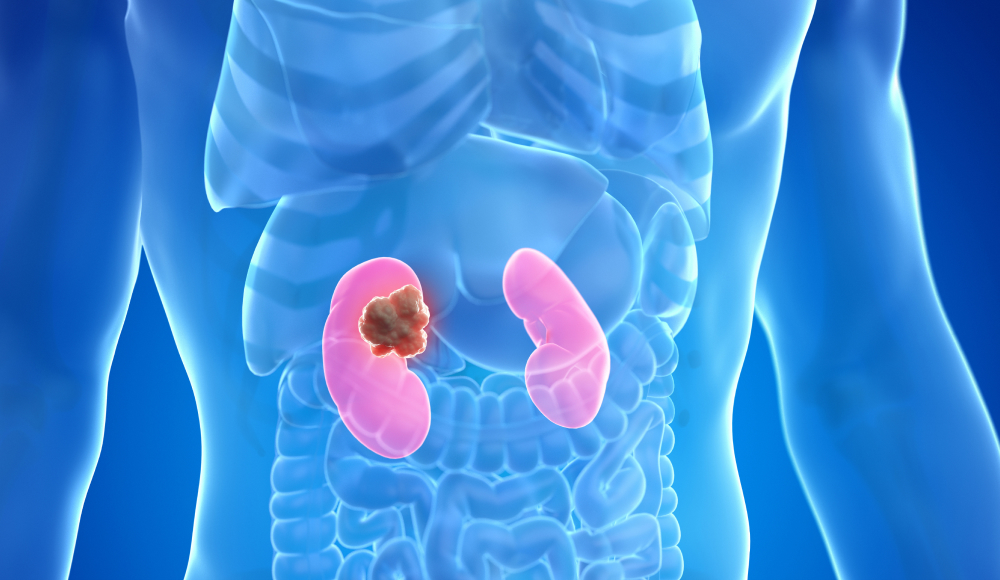

직접 결석 파쇄

최소침습 치료

신장 내 접근

요도 경유

쇄석술로 제거되지 않는 결석, 재발이 잦은 결석, 위치가 나쁜 결석 등 여러 요인을 고려해 가장 효과적인 수술을 제공합니다.